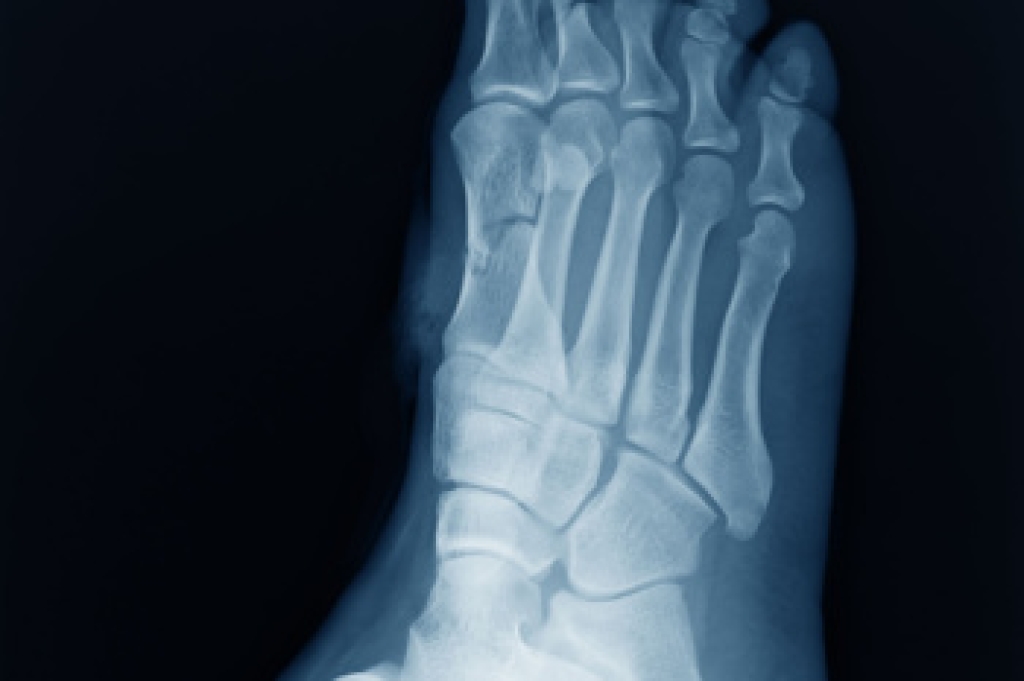

Midfoot arthritis develops when cartilage in the arch of the foot deteriorates, causing pain, stiffness, and swelling. It often results from injury, aging, or long-term wear-and-tear on the joints. Many people notice discomfort during push-off when walking or while standing for long periods of time. Treatment focuses on relieving pain and maintaining mobility. Non-surgical options include wearing supportive footwear, custom orthotics, anti-inflammatory medications, and targeted exercises. When symptoms progress, corticosteroid injections or surgical fusion may be considered to stabilize the joints and reduce pain. If untreated, midfoot arthritis may worsen, leading to chronic pain, deformity, and limited activity. Early care helps preserve function and prevent complications. If you are experiencing ongoing foot pain or stiffness, it is suggested you see a podiatrist for an evaluation and appropriate treatment.